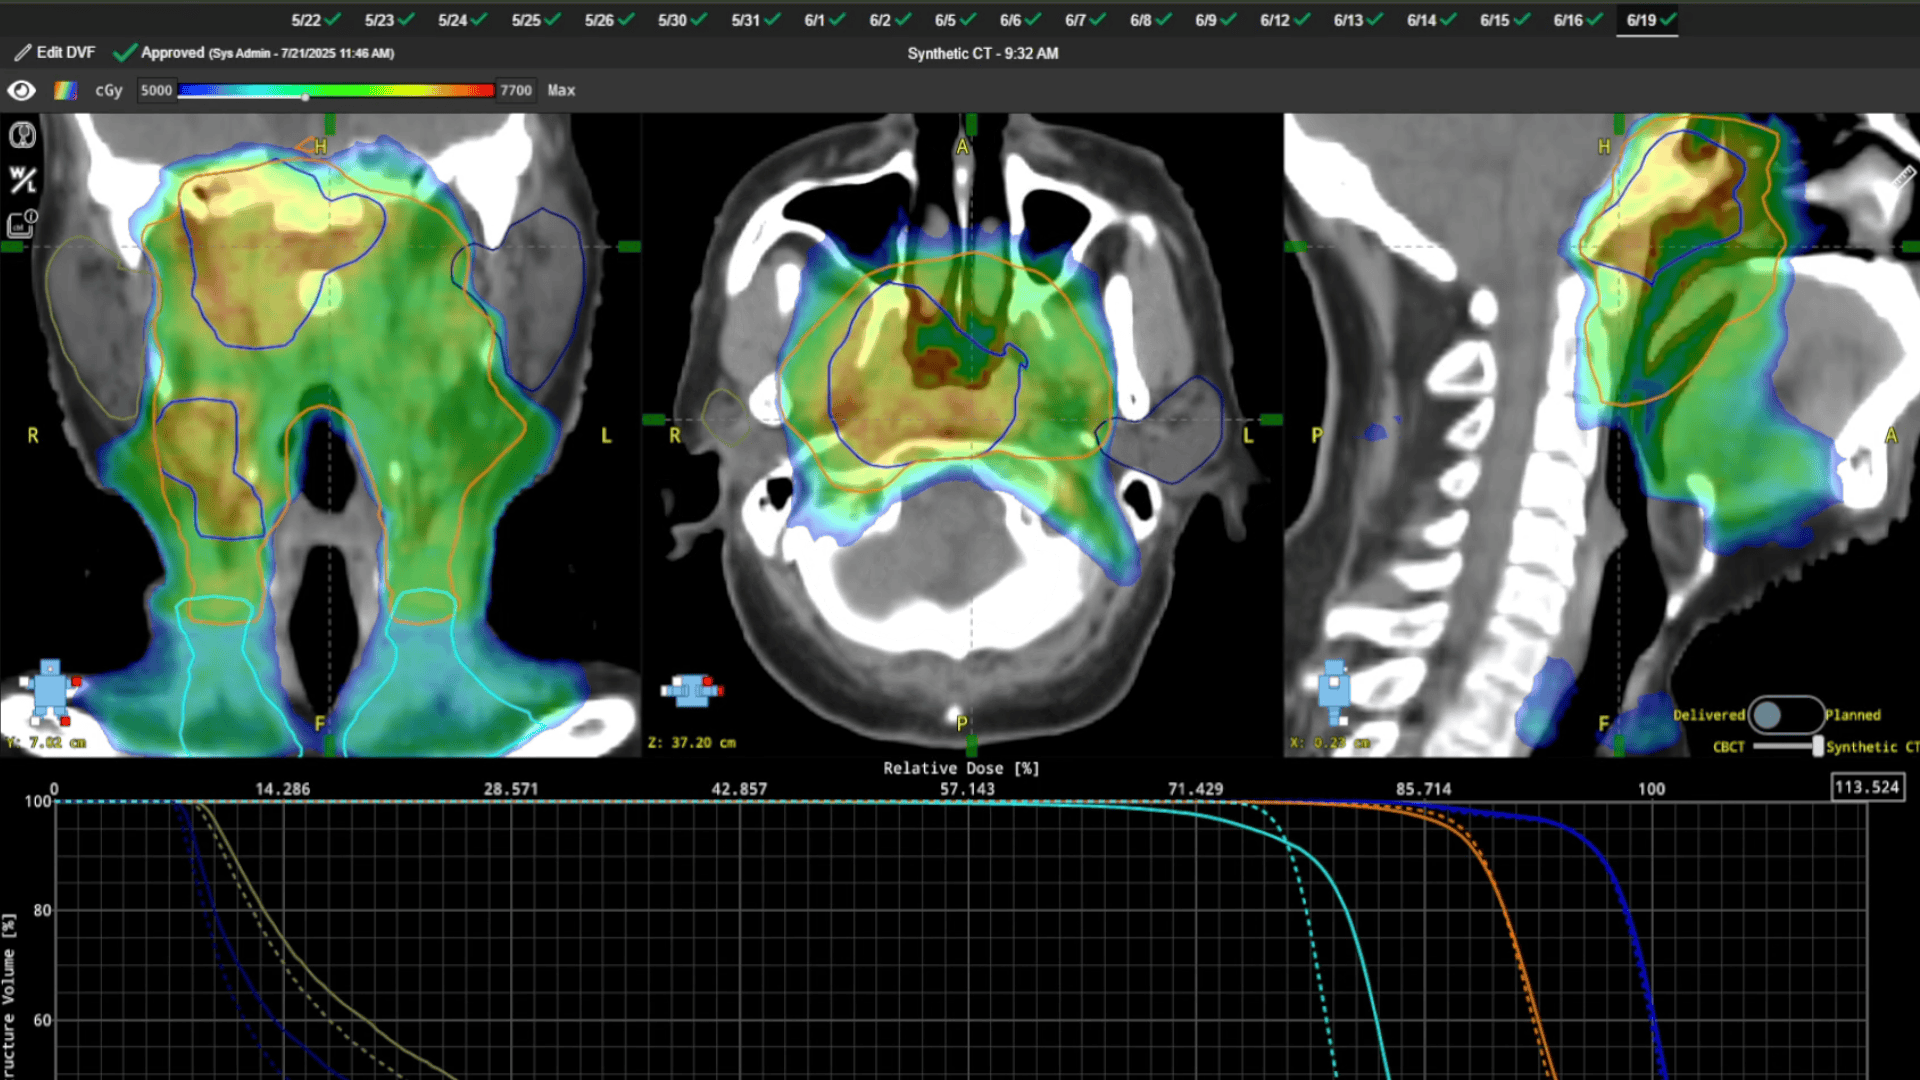

Adaptive QA in ChartCheck showing RadMonteCarlo dose comparison between plan and delivered treatment, with CBCT/Planning CT toggling for real-time visualization of dose accumulation and anatomical changes.

ClearCalc with RadMonteCarlo Dose

Delivers accurate, gold-standard dose recalculations.

The hub for daily treatment insight—tracking delivered dose, DVHs, and anatomical changes in one seamless workflow.